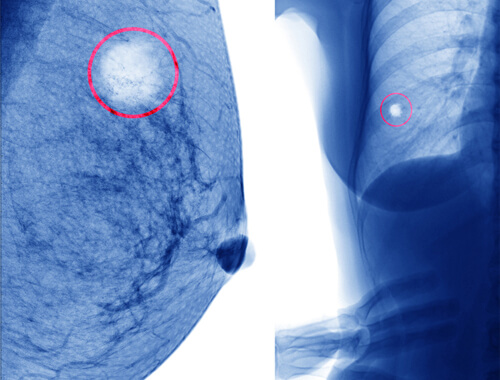

Il trattamento delle cisti implica, all’inizio, il controllo del seno da parte della paziente.

Di solito non è necessaria la chirurgia, ma nel caso in cui si vogliano rimuovere, quelle semplici si eliminano tramite agoaspirazione, mentre quelle complesse con una biopsia e la chirurgia.

Quando nei controlli al seno di routine si riscontra un qualche tipo di cisti, è consigliabile consultare il medico per effettuare una valutazione della stessa tramite una semplice tecnica.

Se è liquida o semisolida, senza altri segnali che indichino qualche aspetto negativo, come ad esempio del sangue, è nel 98% dei casi una cisti semplice.

Queste non si trasformano in cancro maligno e non sono pericolose.

In tal caso, si può realizzare l’aspirazione del suo contenuto e in seguito cercare di evitare i fattori che l’aggravano e che potrebbero averla causata, come quelli che vedremo a seguire.